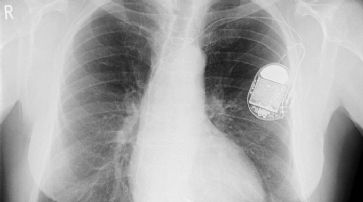

In diesem Jahr beabsichtigte er die Enthüllung von Sicherheitslücken bei Herzschrittmachern - und zwar bei den zugehörigen Funkwartungsprogrammen. Sein eigenes Herz machte leider vorzeitig nicht mehr mit.

Hack-Risiko: «Massenmord» per Herzschrittmacher